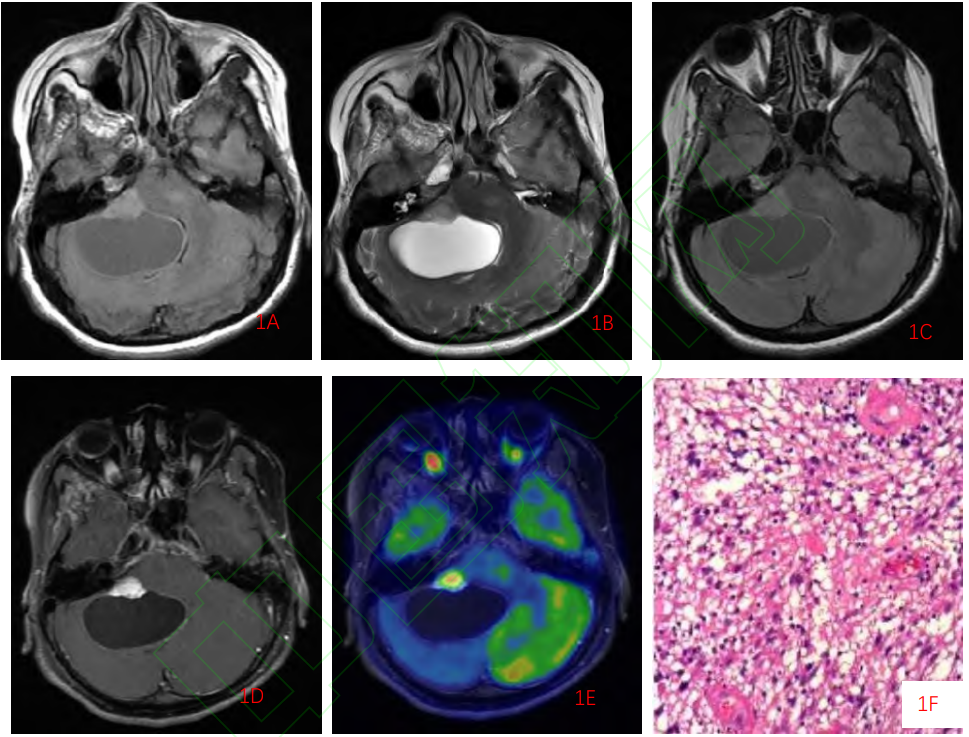

4d73fbf94bb490817626225a71f90e68.png

女,38个月,视交叉-下丘脑-右侧基底节区PMA(WHO Ⅱ级)

A.CT平扫示囊实性肿瘤,继发脑积水、间质性脑水肿,肿瘤实性部分为低密度

B.T1WI示肿瘤的实性部分为低信号

C.T2WI示肿瘤的实性部分为高信号,肿瘤边缘清楚,未见瘤周水肿

D.横断位增强扫描示肿瘤囊性部分的边缘早期即明显强化,呈“花环”样改变,囊变区较大且呈偏心性改变,而肿瘤的实性部分强化较弱,相对延缓

E.矢状位增强扫描后期示肿瘤囊性部分的边缘强化仍然明显,而肿瘤的实性部分呈渐进性强化,后期强化逐渐明显

F.组织学检查显示肿瘤组织基质黏液变明显,瘤细胞多为单极或双极细胞样围绕血管呈放射状排列或呈假菊形团样改变(HE × 200)